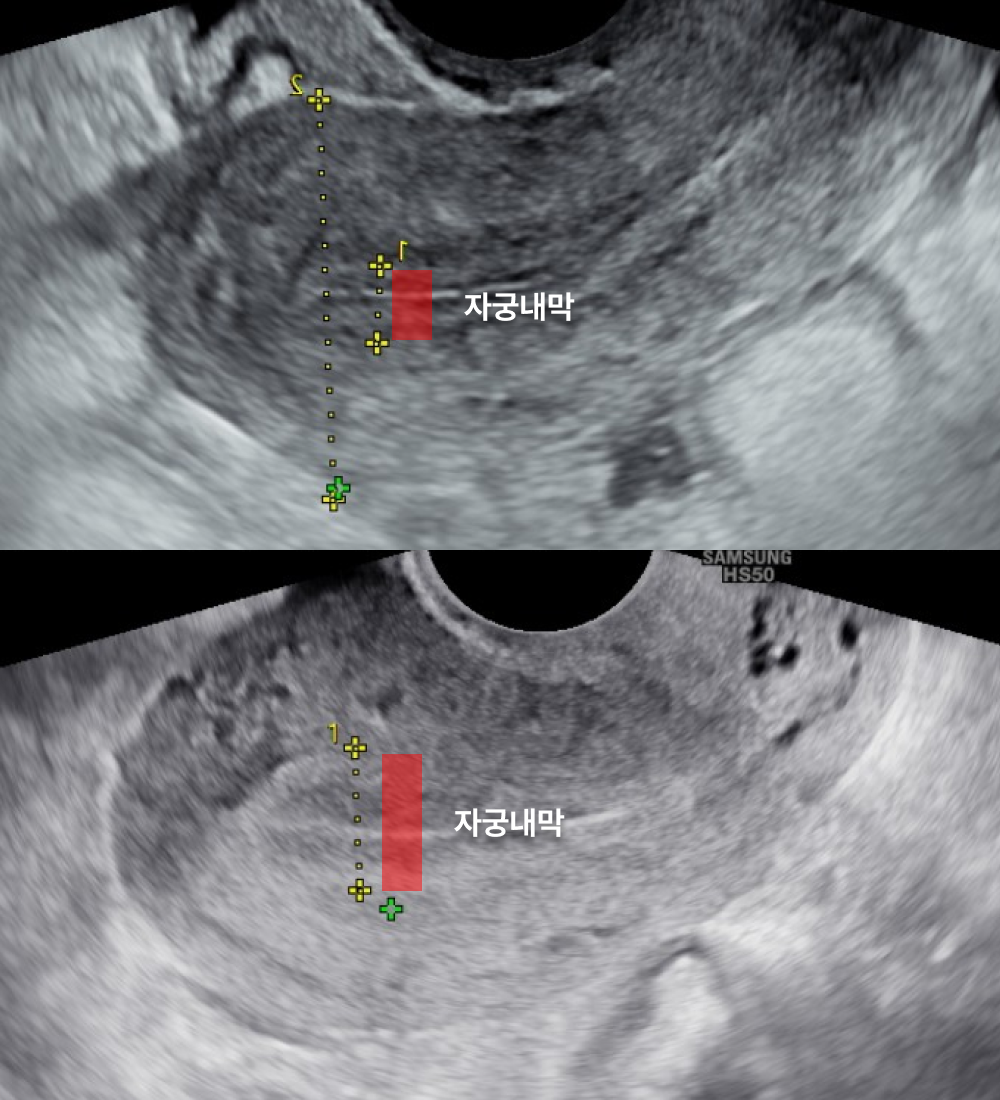

내막재생

Q.

원장님,

자궁내막이 얇다는 진단을 받았어요.

임신이 가능할까요?

네, 내막 재생 치료를 통해

충분히 임신 가능성을 높일 수 있습니다.

자궁내막두께가 얇아지면 배아의 착상이 어려워질 수 있습니다.

특히, 생리불순이 동반되는 경우 자궁내막 상태에 문제가 있을 가능성이 높습니다.

이와 함께 소파술이나 자궁내막염 같은 요인이 자궁내막을 손상하거나 얇아지게 만들 수 있습니다.

하지만, 이러한 문제도 적절한 치료와 관리를 통해 개선할 수 있습니다.

연세아이봄여성의원은 환자 개개인의 상태를 면밀히 분석한 뒤,

맞춤형 내막 재생 치료를 제공하여 착상 환경을 최적화하고, 임신 가능성을 높일 수 있도록 도와드립니다.